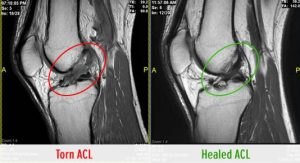

The final twist in the tail of this story is that Mitch never had his reconstructive operation, but he did have a repeat scan in January 2020, and it showed a fully healed ACL! So, there was a real balance between safety and the risk the team took, and the outcome for the patient could not have been better. “We managed him with what could be described as supervised neglect, then put him on the field, and he still ended up healing his ACL. That’s what’s quite interesting” said Flahive.